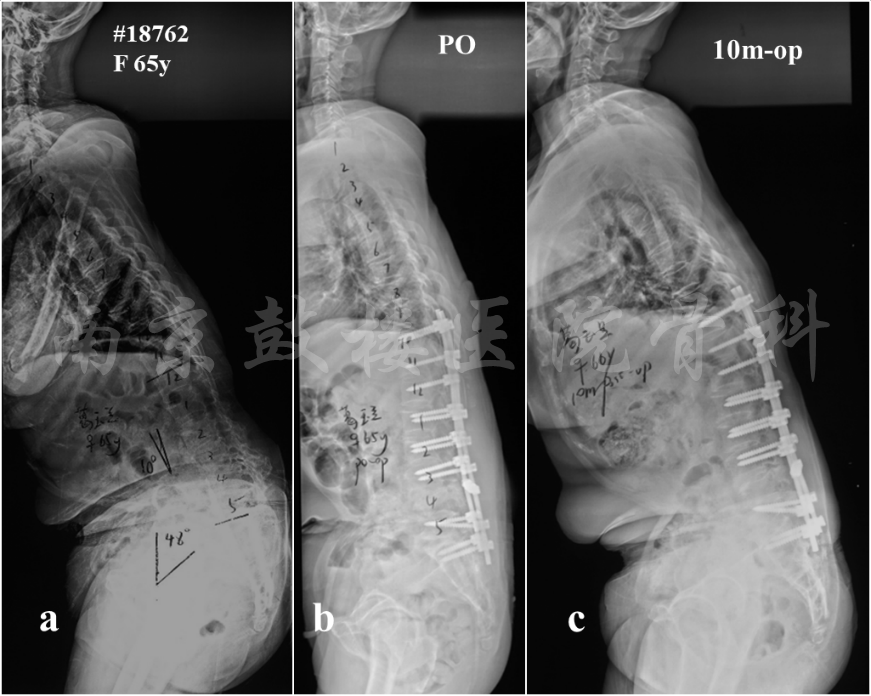

2.重建合适的矢状面平衡

重建合理的矢状面平衡是预防远端内固定失败发生的重要手段。制定手术策略时,SVA应恢复到±5cm的范围内。患者可以通过骨盆后旋或膝关节的屈曲对矢状面失平衡进行代偿,导致骨盆倾斜角(PT)增大,因此术前评估矢状面序列时,患者应保持膝关节伸展,髋部和膝关节同时接触墙壁。术后重建矢状面时,应将PT控制在25°之内。而对于骨盆入射角(PI)较大的患者,则需要重建更大的腰椎前凸。综上,重建合理的矢状面平衡包括SVA<5cm, PT<20°以及PI-LL<±10°,可以有效预防术后远端内固定失败的发生(图4)。

图4 女,65岁。X片示矢状面严重失平衡(a),术前存在右下肢不全瘫;原定手术方案为L4 PSO截骨术,但术中出现MEP事件,且出血较多,因此未行三柱截骨,仅行后路减压及内固定术,术后X片示矢状面形态稍有改善,但是没有达到矫形的目标(b);术后10个月随访,患者躯干失平衡较术后加重,与术前类似(c)。该患者证明如果手术没有很好地重加矢状面形态,将是内固定失败和矫正丢失的重要危险因素